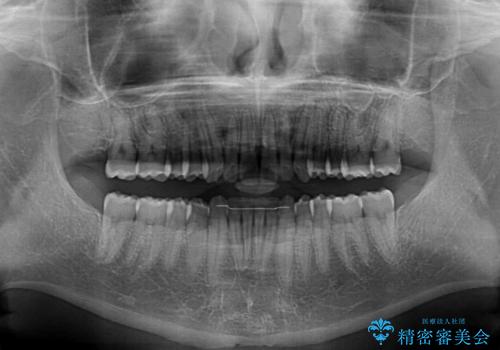

気になっていたデコボコや隙間は改善し、きれいな歯列に整えることができました。

咬合力が非常に強い方であったため、これ以上のディープバイトの改善は困難となりました。